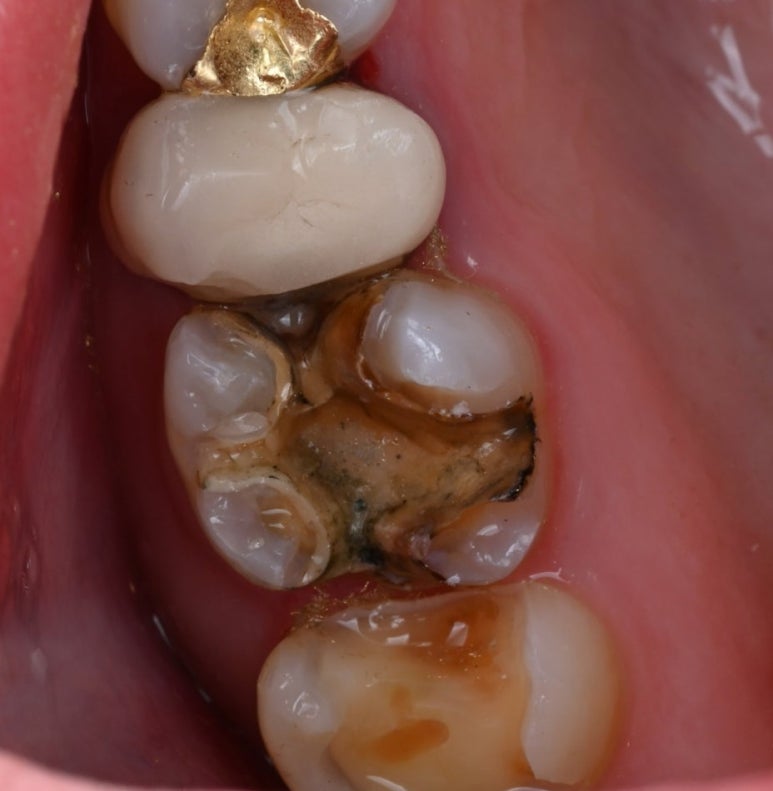

문제가 된 큰 어금니를 치료하던 중,

바로 앞쪽 어금니(#16)의 상태도

심상치 않음을 발견했습니다.

이 치아 역시 금 인레이가 되어 있었는데,

틈새로 비쳐 보이는 내부가

이미 충치로 오염되어 있었습니다.

25.11.11 앞쪽 어금니(#16) 금 인레이 하방에서 발견된 충치

25.11.19 접착 후

25.11.19 교합조정까지 마친 후